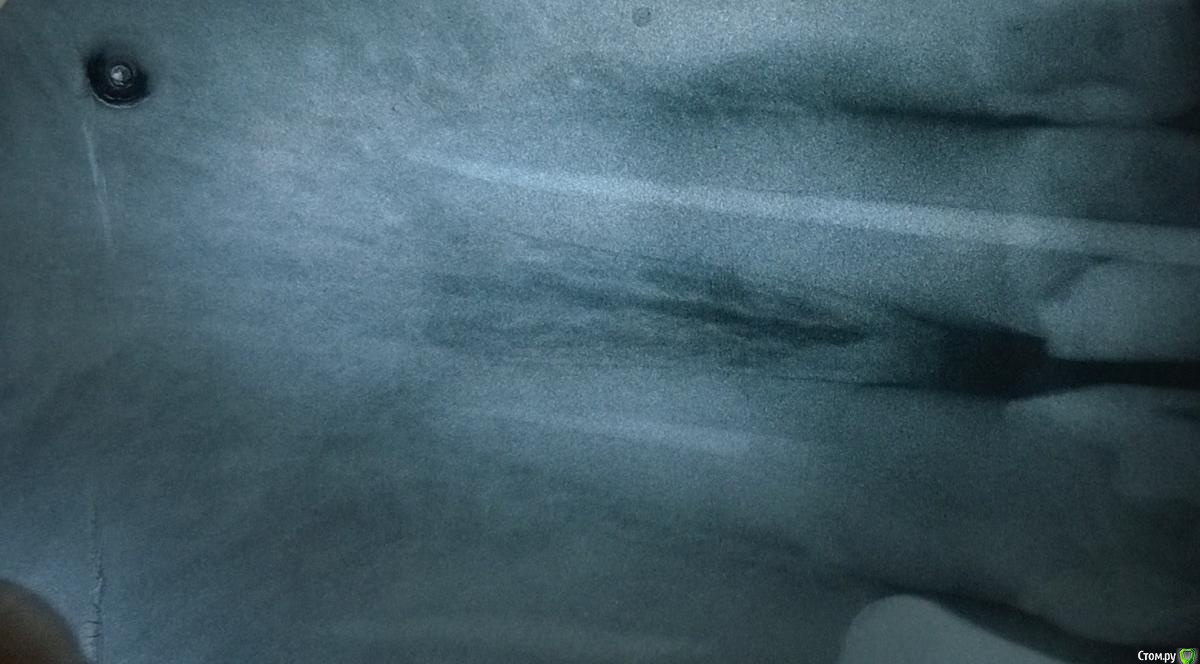

Arcus Опубликовано 6 декабря, 2014 Поделиться Опубликовано 6 декабря, 2014 В этом году закончил интернатуру, поэтому любая критика будет очень полезна Пациентка 58 лет пришла с обострением периодонтита зуба 11, перкуссия резко болезнена, был отек переходной складки, но инфильтрата я не пропальпировал (разрез по переходной складке сделал, но гнойного экссудата не получил , дренаж не ставил).Вот протокол по которому работал:1. Обезболивание2. Наложение коффердама3. Создание доступа (пригодилась эта статья, спасибо Kivilgar)4. Введение RC-prep и прохождение k-file 10 с апекслокатором до 0.0. Измерил линейкой и от этой длины отнял 3 мм, и начал обрабатывать канал на эту длину помощью Protaper S1, S2. Промыл гипохлоритом, подключил апекслокатор и прошел последние 3 мм К файлами 10,15,20,25 сделал рентгеновский снимок. По нему файл был на уровне рентгенологической верхушки, пришлось уменьшить рабочую длину еще на 0,5 мм.5. На полную рабочую длину обработал корневой канал Protaper S1, S2, F1, F2, потом у апекса дорабатывал K файлами NiTi 30,35,40. После каждого файла промывал канал гипохлоритом натрия и проводил рекапитуляцию 10 файлом.6. Медикаментозная обработка перед временным пломбированием. Гипохлорит натрия, высушил пинами, хлоргексидин 2% на 2 мин, высушил пинами, спирт 95%, высушил пинами. Ввел Metapaste, притрамбовал бумажным пином, ватка, временная повязка Кависил. (верхний зуб) Назначил найз по 1 таб 2 р в день, 5 дней и линкомицин 2 кап 3 раза в день 5 дней. (тут прошу совета, нужно ли назначать антибиотик при обострении периодонтита, когда имеется отек переходной складки. При периоститах всегда назначаю антибиотик и НПВС, разрез до кости на всю ширину инфильтрата, промывание и дренирование. Но в данном случае я не смог получить гноя)7. Через 3 дня на осмотре слизистая слиплась из-за того, что не было дренажа, пальпация слабоболезнена, перкуссия слабоболезнена. 8. Через 1,5 недели пациентка жалоб не предьявляет, перкуссия безболезненная, пальпация по переходной складке безболезненная, однако, в проекции верхушки корня я обнаружил плотное, округлое образование слабоболезненное при пальпации. Свища на слизистой нет. Что это может быть? На рентгене особого разрежения костной ткани нет.9. Наложение коффердама, снятие временной пломбы, вымывание кальция гипохлоритом натрия. Фото с мастер-штифтом 40, 0.4. Вот по фотографии явно видно, что штифт немного вышел, хотел же укоротить его на 0,5 мм, ан нет, не сделал. (коффер соскочил во время снятия для рентгена, пришлось без него делать).10. Опять наложил коффер, медикаментозная подготовка перед пломбированием - ЭДТА (Эндожи 2) в канал на 2 мин, немного его активировал гуттаперчевым штифтом. Промыл дистиллированной водой, хлоргексидин 2% вначале мыл, а потом на 2 мин оставил в канале, высушил пинами, промывание гипохлоритом натрия 20 мл с активацией штифтом. Смотрю осадок бурый выходит из канала, ну блин Вот как этого избежать? Водой еще мыть? Причем в первое посещение такого не было. Высушил каналы, промыл 95% спиртом и оставил на 1 мин. Высушил пинами. Осадок очень вреден? Я его потом спиртом вымывал, вроде пины стали чистыми, но как там в дентинных трубочках я не знаю.11. А потом латеральная конденсация, на мастер-файле ввел AH+ в канал, потом добавлял штифты. Отжег в верхней трети, изолирующая из Vetrimer и Кависл.Отправил на рентген, а там такое Паф, да еще вроде штифт вылез, хотя точно не знаю. Оставить так или перепломбировывать? 12. Никогда больше не буду латералить с мастер-штифтом 0.4 конусности, хоть он хорошо клинил в канале, но места для дополнительных штифтов очень мало.Что изменить и дополнить в инструментальной и медикаментозной обработке? 1 Ссылка на комментарий